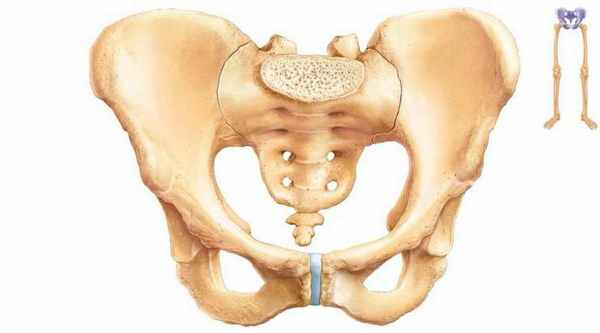

Анатомия подвздошной, лобковой, седалищной кости (тазовой кости)

В данной статье будет рассмотрена анатомия подвздошной, лобковой, седалищной кости, а также анатомия тазовой кости в целом.

Тазовая кость (os coxae) образуется в результате срастания подвздошной, лобковой и седалищной костей и образует пояс нижних конечностей.

Тела этих трех костей в месте соединения образуют:

- Вертлужную впадину (acetabulum) — суставную ямку для головки бедренной кости.

- Полулунную поверхность (facies lunata) — периферическую часть вертлужной впадины.

- Край вертлужной впадины (margo acetabuli) ограничивает полулунную поверхность.

- Ямку вертлужной впадины (fossa acetabuli) — глубокую центральную часть вертлужной впадины.

- Надвертлужную борозду (sulcus supraacetabularis) — находится над вертлужной впадиной.

Анатомия седалищной кости

Седалищная кость (os ischii) имеет тело, составляющее нижнюю часть вертлужной впадины. Кроме тела, для седалищной кости характерны следующие костные образования:

- Ветвь седалищной кости (ramus ossis ischii) — отходит от тела вниз.

- Седалищный бугор (tuber ischiadicum) — утолщение ветви.

- Седалищную ость (spina ischiadica) — направляется кзади от тела седалищной кости, а также разделяет:

- большую седалищную вырезку (incisura ischiadica major),

- малую седалищную вырезку (incisura ischiadica minor)

Ветвь седалищной кости (ramus ossis ischii), соединяясь с нижней ветвью лобковой кости, ограничивает запирательное отверстие (foramen obturatum), в верхнепереднем крае которого находится запирательная борозда (sulcus obturatorius).